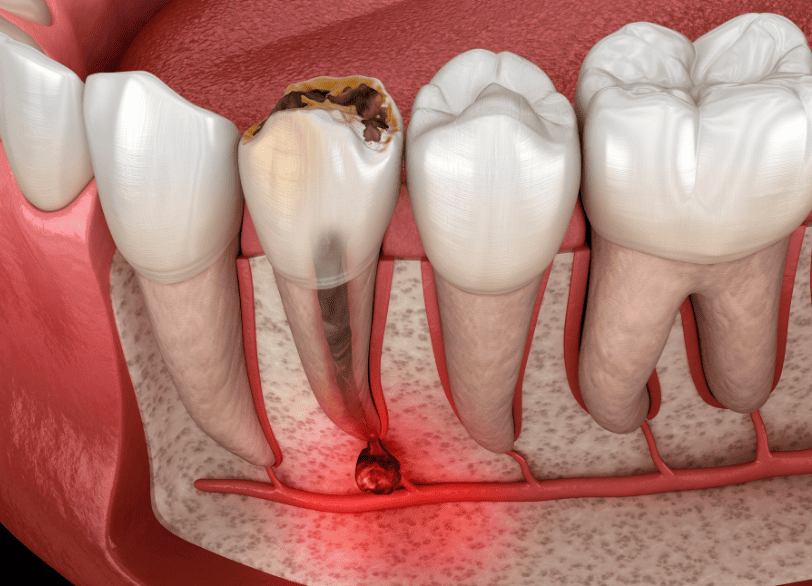

歯の内部には、神経や血管が通っている「歯髄(しずい)」と呼ばれる組織があります。

虫歯菌がエナメル質や象牙質を溶かし、この歯髄にまで到達すると、激しい炎症と痛みを引き起こします(歯髄炎)。

さらに放置すると、神経は壊死し、細菌は根の先から顎の骨へと広がり、膿の袋(根尖病巣)を作ります。

このように、細菌感染が歯の深部にまで及んだ場合、自然治癒することはありません。

感染源である神経や汚染物質を物理的に取り除き、管の中をきれいに掃除して消毒し、再び細菌が入らないように薬で密閉する必要があります。

これが根管治療です。